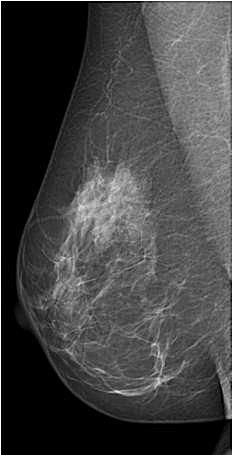

Die Mammographie ist ein bildgebendes Verfahren zur Untersuchung der Brust.

Als „Screeningmammographien“ werden Untersuchungen bei beschwerdefreien Frauen bezeichnet, die zum Zweck der Früherkennung von Brustkrebs dienen. Als „diagnostische Mammographien“ werden jene Untersuchungen bezeichnet, die zur Abklärung von Beschwerden (z.B. Schmerzen, tastbare Knoten, Flüssigkeitsabsonderungen aus der Brustwarze) durchgeführt werden.

Zum Zweck der Brustkrebsfrüherkennung hat sich die Mammographie als jene Methode erwiesen, mit der Frühstadien von Brustkrebs in einem sehr hohen Prozentsatz erkannt werden können. Bei Frauen mit sehr dichtem Drüsengewebe können bösartige Herde in der Mammographie allerdings verborgen bleiben. In diesen Fällen wird eine ergänzende Ultraschalluntersuchung durchgeführt, um eventuelle, im dichten Gewebe liegende Tumore aufzufinden. Eine alleinige Ultraschalluntersuchung ist zum Zweck der Früherkennung nicht ausreichend, da subtile Zeichen von Brustkrebs, wie z.B. feine Verkalkungen oder Asymmetrien im Drüsengewebe durch den Ultraschall nicht effizient zu beurteilen sind.